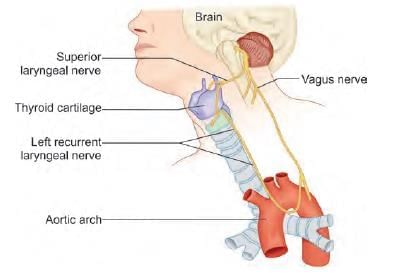

Which of the following nerve is least injured in thyroid surgery? (AIIMS June 2020)

Which of the following arrow marked nerves, if injured present with paradoxical breathing? (INI-CET Nov 2020)